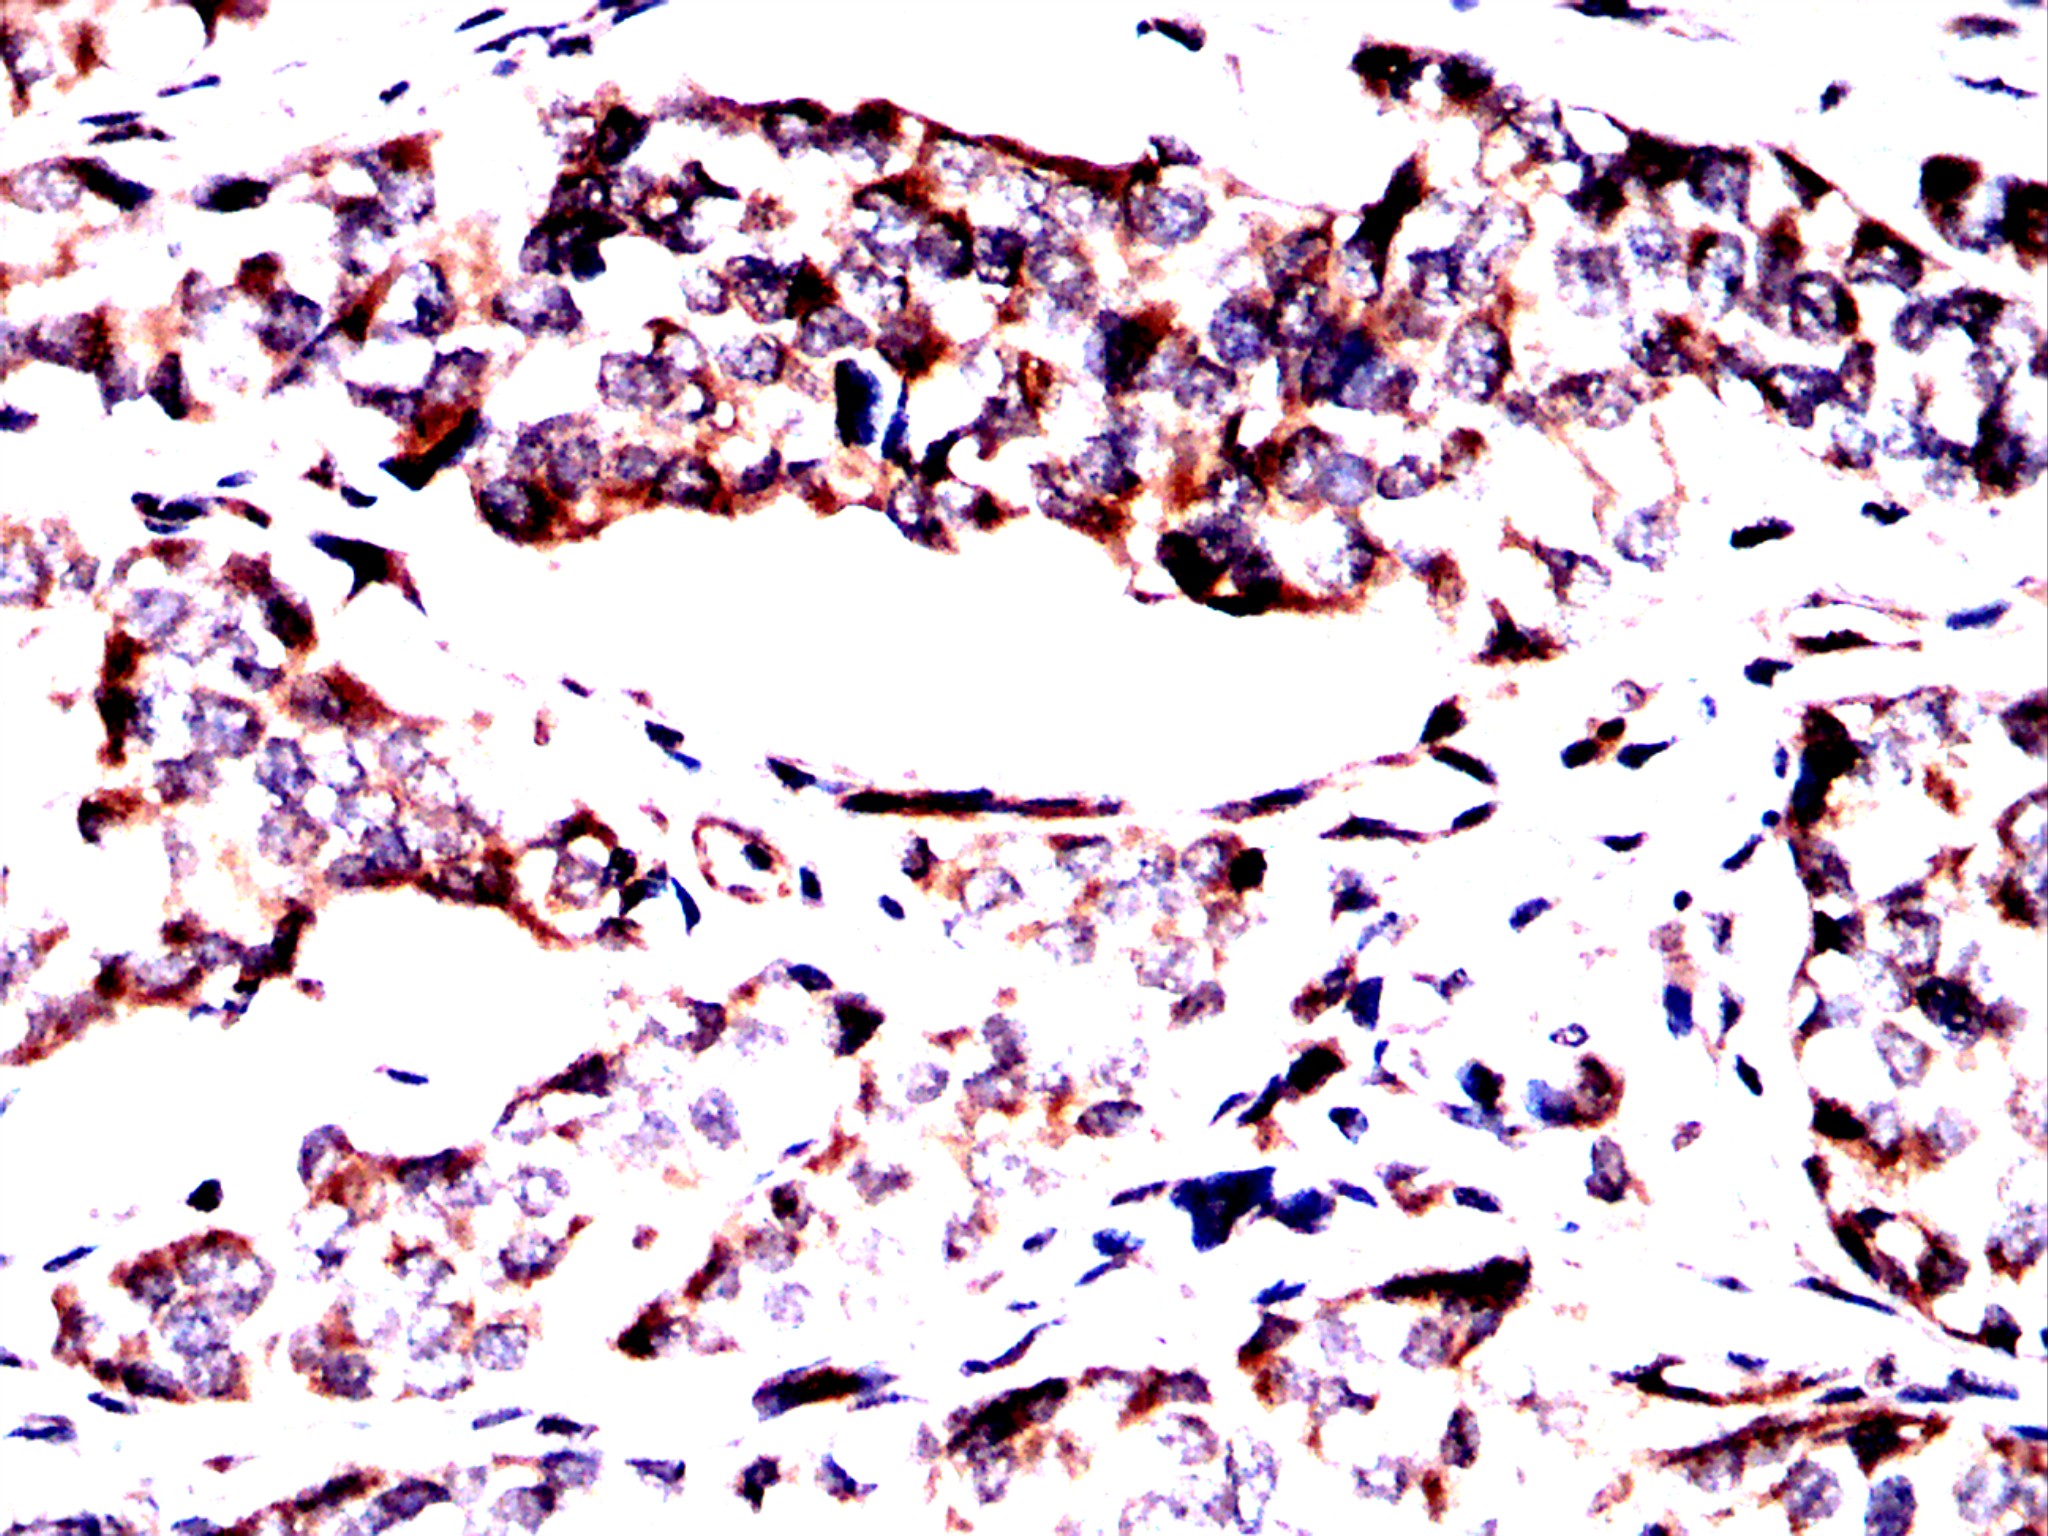

Immunohistochemical analysis of paraffin-embedded lung cancer tissues using Pelo antibody with DAB staining. Pre-treat the sections with heat-mediated antigen retrieval using sodium citrate buffer (pH 6.0) (OM750020) for 2 minutes. Wash the sections with ddH₂O and PBS (OM750003). Block the tissue with 10% non-immune goat serum(OM760028) at room temperature for 30 minutes. Incubate the tissue with the primary antibody diluted at a ratio of 1:1500 at 4°C overnight. At room temperature, dilute the secondary antibody, Goat Anti-Rabbit IgG(H&L)-HRP (OM644332), at a ratio of 1:200 and incubate for one hour. Use DAB(OM760029)as the chromogenic agent. Counterstain the tissue with hematoxylin, and mount the tissue sections with neutral gum.IHC

Immunohistochemical analysis of paraffin-embedded lung cancer tissues using Pelo antibody with DAB staining. Pre-treat the sections with heat-mediated antigen retrieval using sodium citrate buffer (pH 6.0) (OM750020) for 2 minutes. Wash the sections with ddH₂O and PBS (OM750003). Block the tissue with 10% non-immune goat serum(OM760028) at room temperature for 30 minutes. Incubate the tissue with the primary antibody diluted at a ratio of 1:1500 at 4°C overnight. At room temperature, dilute the secondary antibody, Goat Anti-Rabbit IgG(H&L)-HRP (OM644332), at a ratio of 1:200 and incubate for one hour. Use DAB(OM760029)as the chromogenic agent. Counterstain the tissue with hematoxylin, and mount the tissue sections with neutral gum.